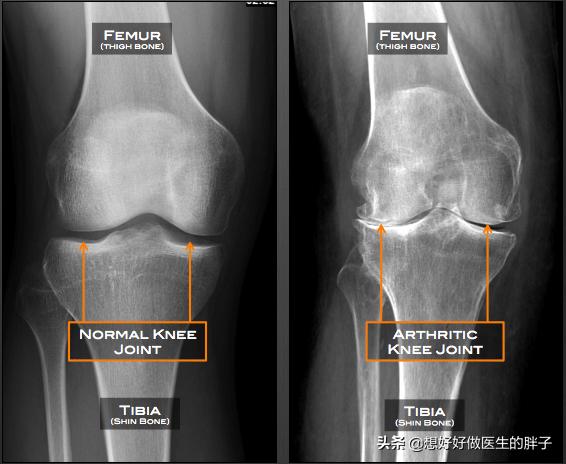

●Röntgenuntersuchung des KniegelenksMit der Röntgenaufnahme des Knies kann festgestellt werden, ob der Patient an einer signifikanten Osteoporose leidet und ob eine signifikante Verengung des Gelenkspalts vorliegt.OsteoarthritisIst die Existenz vonRheumatoide Arthritis.Oder ein anderes häufiges Knieproblem.

Wie Sie auf dem Bild unten sehen können, ist es typisch, dass sich die Gelenke entwickelt habenSichtbare Lücken, schmale Knochenbildung, einhergehend mit einer schwereren GelenkosteoporoseWenn ein solcher Patient offensichtliche Missempfindungen und Schmerzen hat, wird der Patient durch intraartikuläre Injektionen von Natriumvitrat oder ständige orale Analgetika, die dem Patienten nicht wirklich helfen, das Problem zu lösen, in starke Schmerzen versetzt.

Es wird empfohlen, in solchen Fällen Röntgenaufnahmen des Kniegelenks anzufertigen, um die Möglichkeit einer Arthrose abzuklären. Die Arthrose ist durch folgende Merkmale gekennzeichnet: Sie tritt an gewichtstragenden Gelenken wie den Knien und Hüften auf; die Gelenkschmerzen sind mit Aktivität verbunden und werden durch Ruhe gelindert; nach längerer Ruhe der Gelenke kommt es zu einer vorübergehenden Steifheit und einer lokalisierten Dauer. Danach verschwindet sie für höchstens 30 Minuten; in schweren Fällen treten Gelenkschmerzen und Bewegungseinschränkungen auch in Ruhe auf; die betroffenen Gelenke sind oft von Zärtlichkeit, Knochenhypertrophie, Knochenreibung und bei einigen Patienten von Deformierungen begleitet. Diese Krankheit tritt nicht nur in einem Teil auf, der ganze Körper der Gelenke des Körpers sind möglich Arthritis.

- Frikativ--Wenn der Gelenkknorpel stark abgenutzt ist, verlieren die Enden der subchondralen Knochen den Knorpelschutz, und bei direkter Reibung ertönt ein leises, heiseres Reibegeräusch; die in der Gelenkhöhle umherwandernden Knorpeltrümmer verursachen auch leicht ein Einklemmen, was zu einem Gelenkreibungsgeräusch führt. Die Patienten sollten es von einem normalen physiologischen Knacken unterscheiden, das Beurteilungskriterium ist sehr einfach, ein pathologisches Knacken wird oft von Gelenkbeschwerden begleitet.